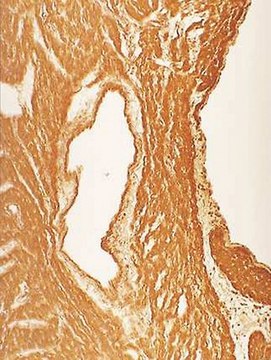

Nitrotyrosine has been identified as an indicator of cell damage and inflammation, as well as of the production of NO. It is believed that measuring the concentration of nitrotyrosine will serve as a marker for damage caused by NO in the cell. Previous studies have shown that nitrotyrosine has been found in inflammatory conditions such as atherosclerotic plaques and rheumatoid arthritis, among others

Anti-Nitrotyrosine Antibody, clone 1A6 detects level of Nitrotyrosine & has been published & validated for use in IC, IH, IP & WB.

Immunohistochemistry: Human Alzheimer disease brain sections (Methacarn fixed), mouse liver